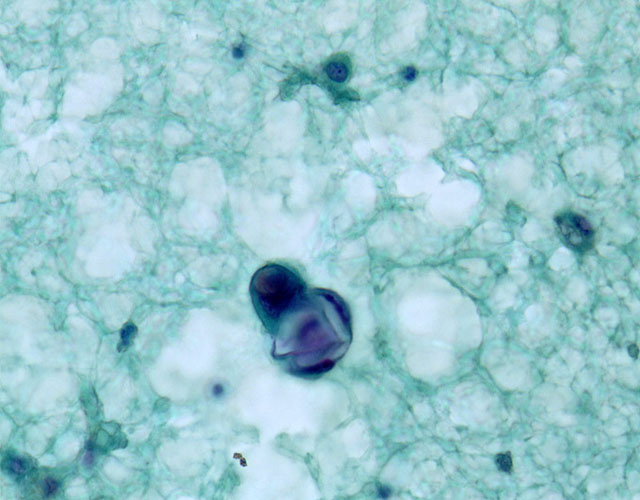

結合性強度と核の突出が見られる